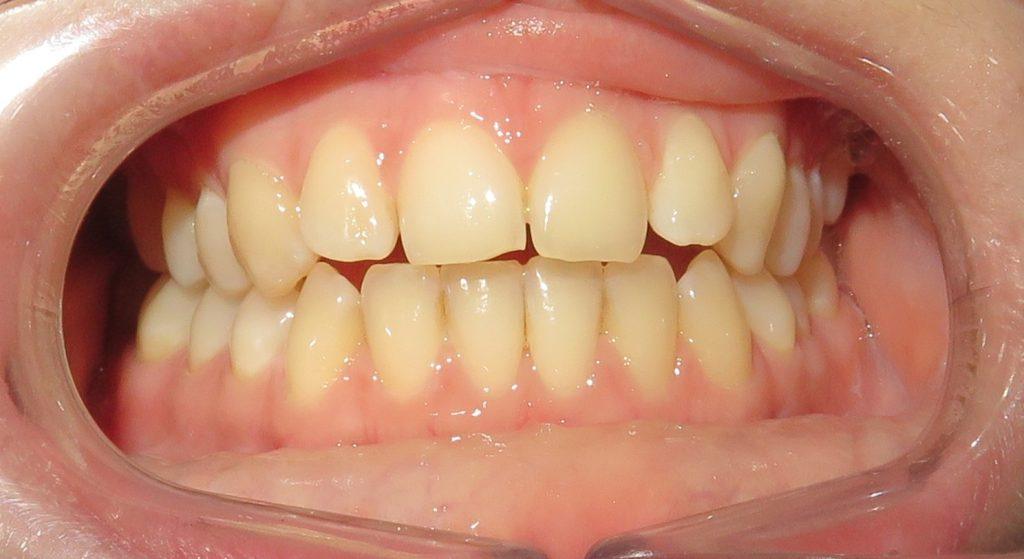

Pacjentka zgłosiła się do nas z takimi problemami, jak:

❌ zwężone łuki zębowe,

❌ tyłozgryz,

❌ głęboki zgryz,

❌ stłoczenia,

❌ zrotowane i starte zęby

Pod opieką Agnieszki Łukowicz, Master of Science Orthodontics została poddana zaawansowanemu leczeniu aparatem stałym ligaturowym, Dzięki czemu udało się osiągnąć znaczące zmiany:

✅poszerzenie luków zębowych,

✅korekta tyłozgryzu,

✅rozwiązanie stłoczenia,

✅odrotowanie zrotowanych zębów,

✅odbudowa startych zębów.

Efekt estetyczny został dopełniony przez wybielanie zębów i odbudowę kompozytową wykonaną przez dr Monikę Niewitecką.

Przedstawiamy piękny i zdrowy uśmiech naszej Pacjentki!